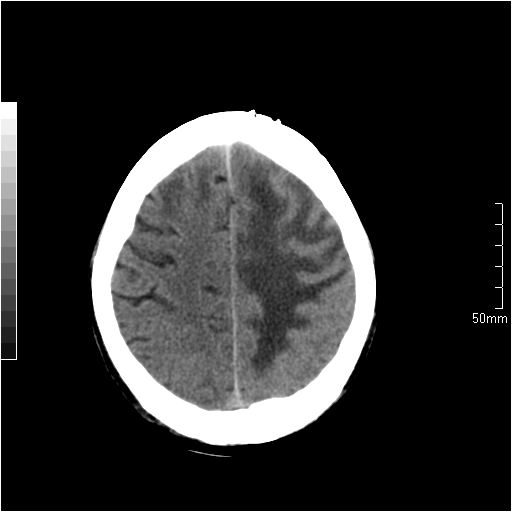

以下是引用天南地北在2007-6-25 12:39:00的发言:[br]有占位效应[br]支持术后复发

以下是引用zjzjr在2007-6-25 12:38:00的发言:[br]左侧复发,右侧转移。